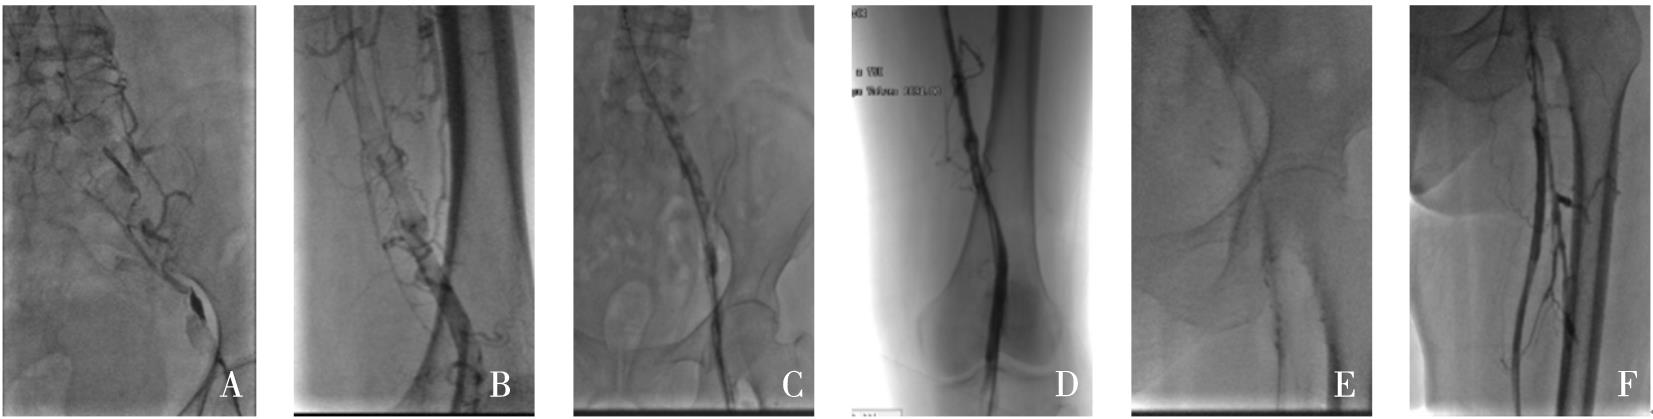

该文追踪1例低叶酸血症患者6年,观察患者体内血栓的动态演变过程。对该例患者进行了叶酸水平、同型半胱氨酸、维生素B12水平监测,同时监测患者的颈动脉超声、下肢动脉超声、头颅磁共振成像和磁共振血管成像,并获得患者的基因学检测结果。第1年,患者出现了左侧大脑中动脉皮质支闭塞(叶酸2.23 ng/mL)。第2年,患者出现了左下肢深静脉血栓(叶酸2.58 ng/mL)。第3年,患者出现左侧颈内动脉颅内段大部分闭塞(叶酸2.16 ng/mL)。第4年,患者出现右下肢深静脉血栓+左侧颈内动脉颅外段狭窄+右下肺静脉血栓形成(叶酸2.27 ng/mL),此时启动了补充叶酸治疗。第5年,患者未再新发血栓。采用DNA微阵列法检测发现,该例患者基因组中MTHFR基因677位为T/T纯合型(突变型)。第6年,患者死于肺炎。该类型突变的患者会出现低叶酸血症,导致快速侵袭性、全身动静脉多发性血栓,补充叶酸治疗可能有效。

A patient with hypofolatemia was followed up for 6 years to observe the dynamic evolution of thrombus. The levels of folic acid, homocysteine, and vitamin B12 were monitored, as well as carotid artery ultrasound, lower extremity arterial ultrasound, cranial MRI, and MRA, and genetic testing results were obtained. The patient experienced occlusion of the cortical branch of the left middle cerebral artery (folic acid 2.23 ng/mL) in the first year, deep vein thrombosis of the left lower extremity (folic acid 2.58 ng/mL) in the second year, and occlusion of most of the intracranial segment of the left internal carotid artery (folic acid 2.16 ng/mL) in the third year. In the fourth year, the patient experienced deep vein thrombosis of the right lower extremity, stenosis of the extracranial segment of the left internal carotid artery, and venous thrombosis of the right lower lung, with a folic acid level of 2.27 ng/mL, and folate supplementation was initiated at this time. New-onset thrombus was not observed in this patient in the fifth year. DNA microarray analysis showed T/T homozygous type (mutant type) at the 677 locus of the MTHFR gene. The patient died of pneumonia in the sixth year. Patients with such mutation may develop hypofolatemia, leading to rapidly aggressive multiple arteriovenous thrombosis throughout the body, and folate supplementation might be an effective treatment method.

图2 左下肢静脉造影Fig.2

图7 计算机体层成像血管造影图像Fig.7